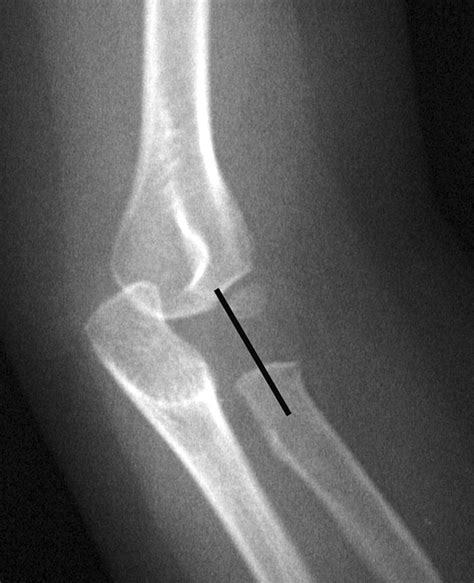

Diagnosing nursemaid elbow typically involves a physical examination by a healthcare provider. The provider will assess the child's arm and elbow for signs of injury and may perform a gentle manipulation to confirm the diagnosis. In some cases, a Nursemaid Elbow Xray may be ordered to rule out other potential injuries, such as fractures or dislocations. However, X-rays are not always necessary for diagnosing nursemaid elbow, as the injury does not typically show up on imaging studies.

In some cases, nursemaid elbow may be mistaken for other injuries, such as fractures or dislocations. It is important to seek medical attention if your child experiences pain or limited movement in the elbow, even if you are not sure what caused the injury. A healthcare provider can perform a thorough evaluation and order a Nursemaid Elbow Xray if necessary to rule out other potential injuries.